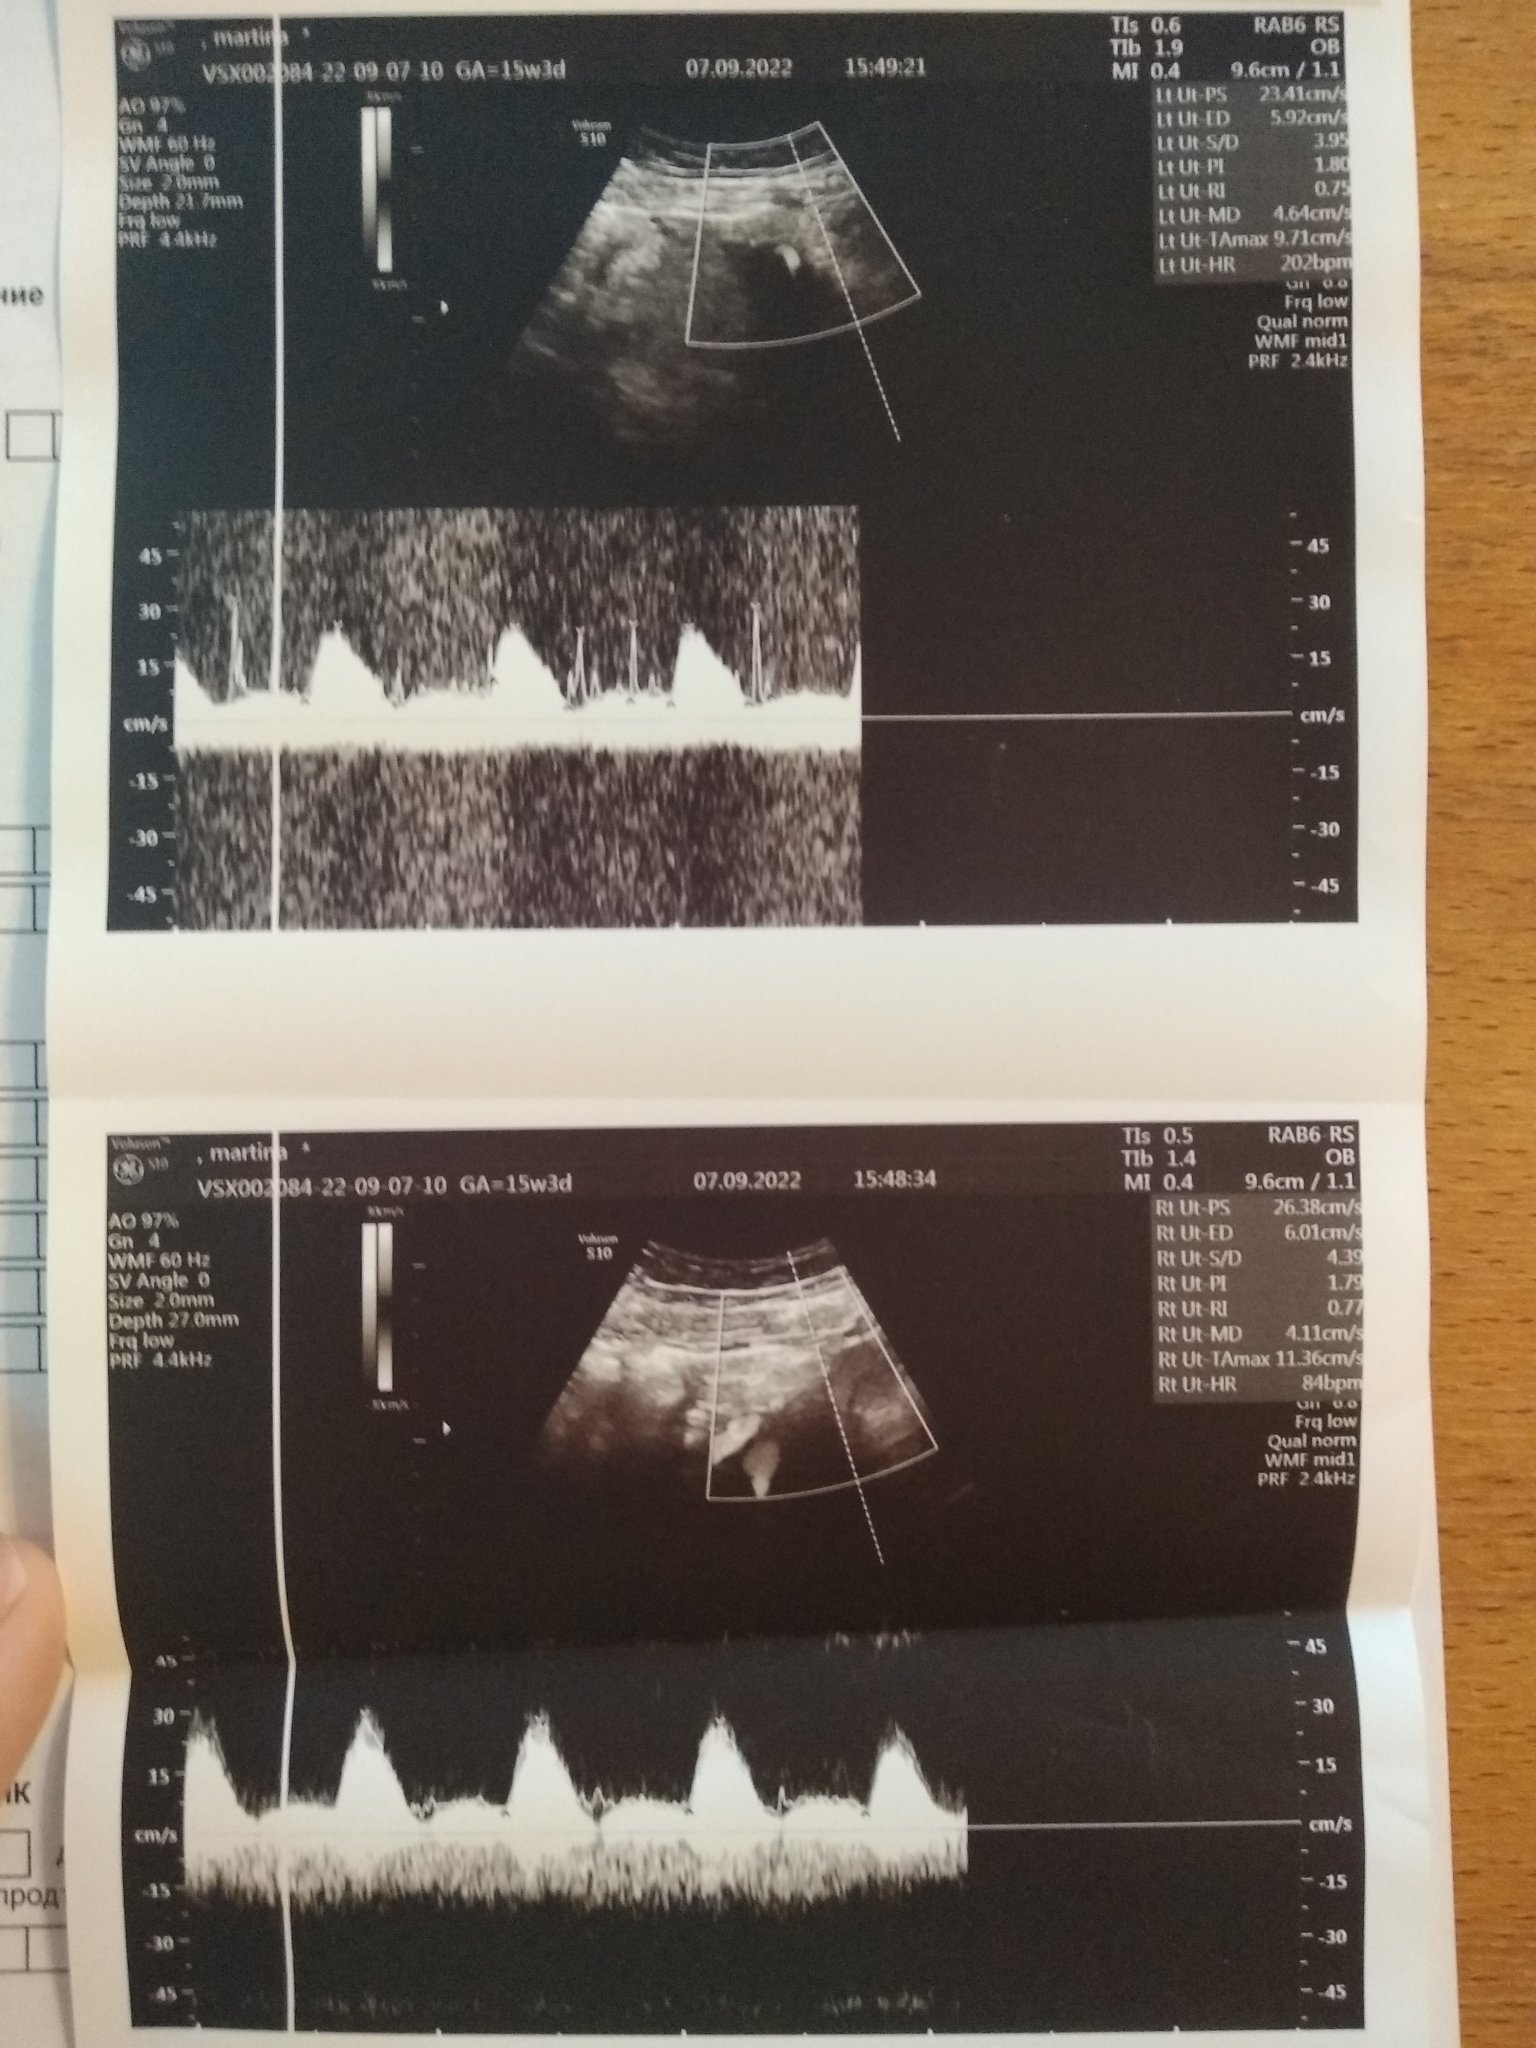

Тази бременност проследяващата лекарка включи клексан 0.4 от първия преглед в 6гс. В 12гс направихме фм при лекар, на който много вярвам, на нея не й хареса кръвотока към матката (pi 2.6 в едната артерия) и включи 150мг аспирин. Само с клексана коагулацията беше супер, с аспирина започнах да посинявам и синките стоят със седмици, по корема също от инжекциите и нямам къде да ги бия вече, а съм в 4м. Тази седмица 15гс бях на преглед при проследяващата аг. Питах я дали можем да спрем клексана, и тя го спря. Защото имам една износена бременност без него, защото рискът при мен бил в 1 триместър. Въпреки че кръвотока не й хареса много (pi около 1.8  ). Бих прикачила снимки от последния преглед, защото тя не се обяснява много.